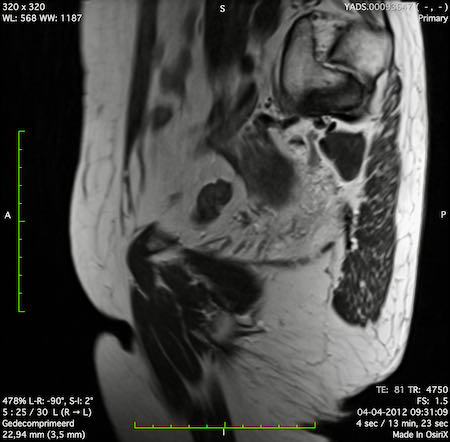

Hình ảnh

Các hình ảnh được cung cấp cho thấy ung thư biểu mô tế bào nhẫn với tình trạng dày lan tỏa thành trực tràng, hình ảnh bia bắn điển hình, và sự xâm lấn mỡ mạc treo trực tràng.